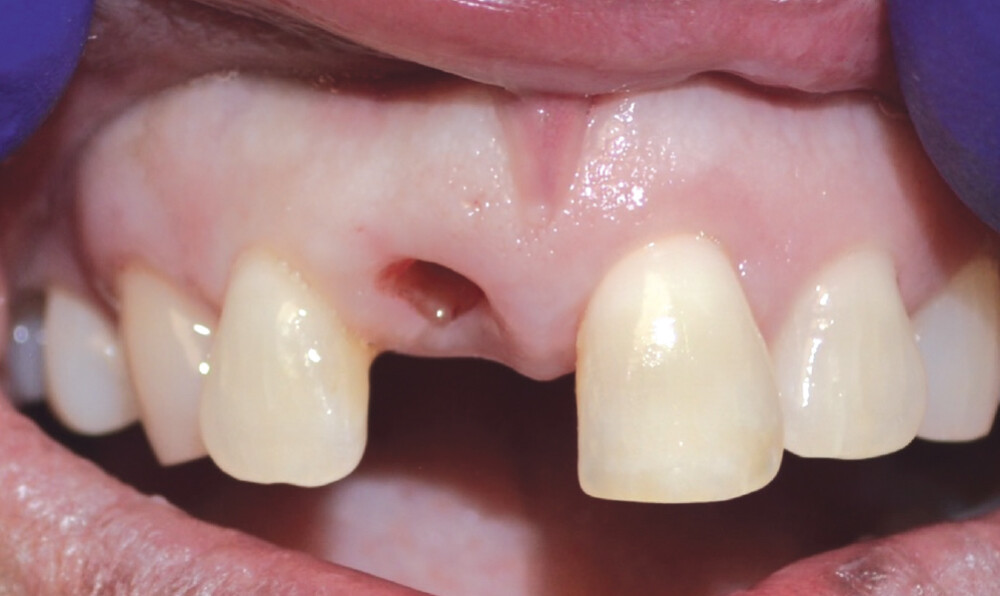

The patient presented with a failing tooth #8. After extraction, the socket shape resembled a triangle. Because of the round shape of the dental implant, there were gaps between the implant body and the alveolus which required grafting.